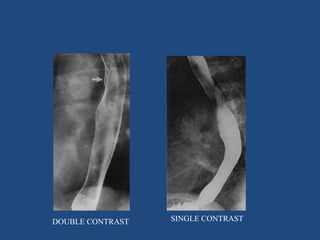

1. SINGLE CONTRAST- single contrast medium

2. DOUBLE CONTRAST- two contrast media

• Ba sulphate suspension (+ve contrast )

• Air (-ve contrast)

SINGLE CONTRAST

• Elderly & uncooperative pts

• Low concentration

• Poor mucosal coating

• Less sensitive for polyps,

erosions, linear ulcerations,

superficial gastric ca, subtle

mucosal abnormalities

DOUBLE CONTRAST

• younger

• higher conc.

• good mucosal coating

• more sensitive polyps &

small mucosal lesions

DOUBLE CONTRAST SINGLE CONTRAST